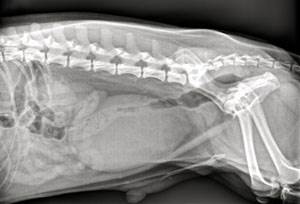

На приеме врач осматривает пациента, собирает данные о перенесенных заболеваниях, проведенной терапии. При пальпации брюшной полости выявляется перерастянутый атоничный мочевой пузырь. Далее проводится подробный неврологический осмотр, проверяются рефлексы. Это позволяет определить степень неврологического дефицита, локализацию первичной проблемы (например, выясняется, какой сегмент спинного мозга оказался поврежден).

При необходимости мочевой пузырь катетеризируют. Так проверяется проходимость мочеиспускательного канала, удаляется избыток мочи.

Лабораторная диагностика включает в себя общий клинический и биохимический анализы крови, анализ мочи. Проводится ультразвуковое исследование органов брюшной полости.

Дальнейший поиск повреждений позвоночника, спинного мозга включает в себя рентгенографию, миелографию, КТ и МРТ.